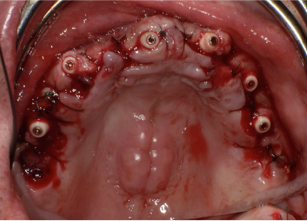

中途半端に悪い歯を残すと、後々治療が大変になるので思い切ってすべての歯を抜歯します

術直後の写真です

オールオン6本のインプラントをいれました

初期固定もよかったので即時荷重をおこなっています